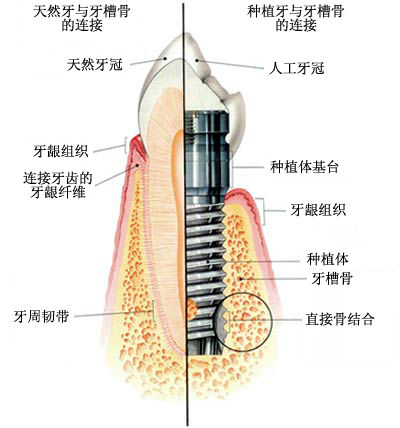

姚立平专家说,所谓的种植牙,就是指在牙槽骨内植入生物材料制成的人工牙根、用以支持和固定牙冠的缺牙修复方式,其功能与外观几乎与真牙一样,被称为人类的“第三副牙齿”。

2、手术开始,先在牙槽骨上备孔并植入种植体(人工牙根),然后等待3~6个月的骨结合期。

3、安装愈合基台使种植体穿出牙龈,等待2~3周让软组织成形。

4、软组织成形后用永久基台换下愈合基台,较后安装固定种植牙冠便完成了种植牙手术。

2、牢固:因为种植牙的人工牙根是植入在牙槽骨上,就像真牙扎根于口腔一样。